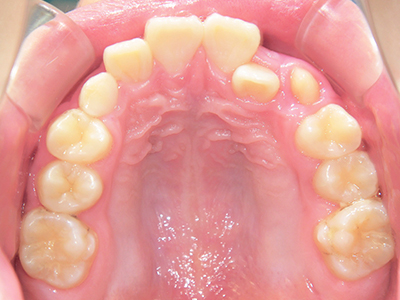

ないき歯科クリニックでは、上あごの成長不足を補い、鼻呼吸を獲得しつつ歯列を整え、将来のお口をより健康な状態にすることをゴールに定める矯正治療をおこなっています。

矯正装置を装着し、調整しながら少しずつ歯を移動させ、歯並びを整えていきます。

状態によって家庭でのトレーニングが必要な場合もあり、治療期間も個人差があります。